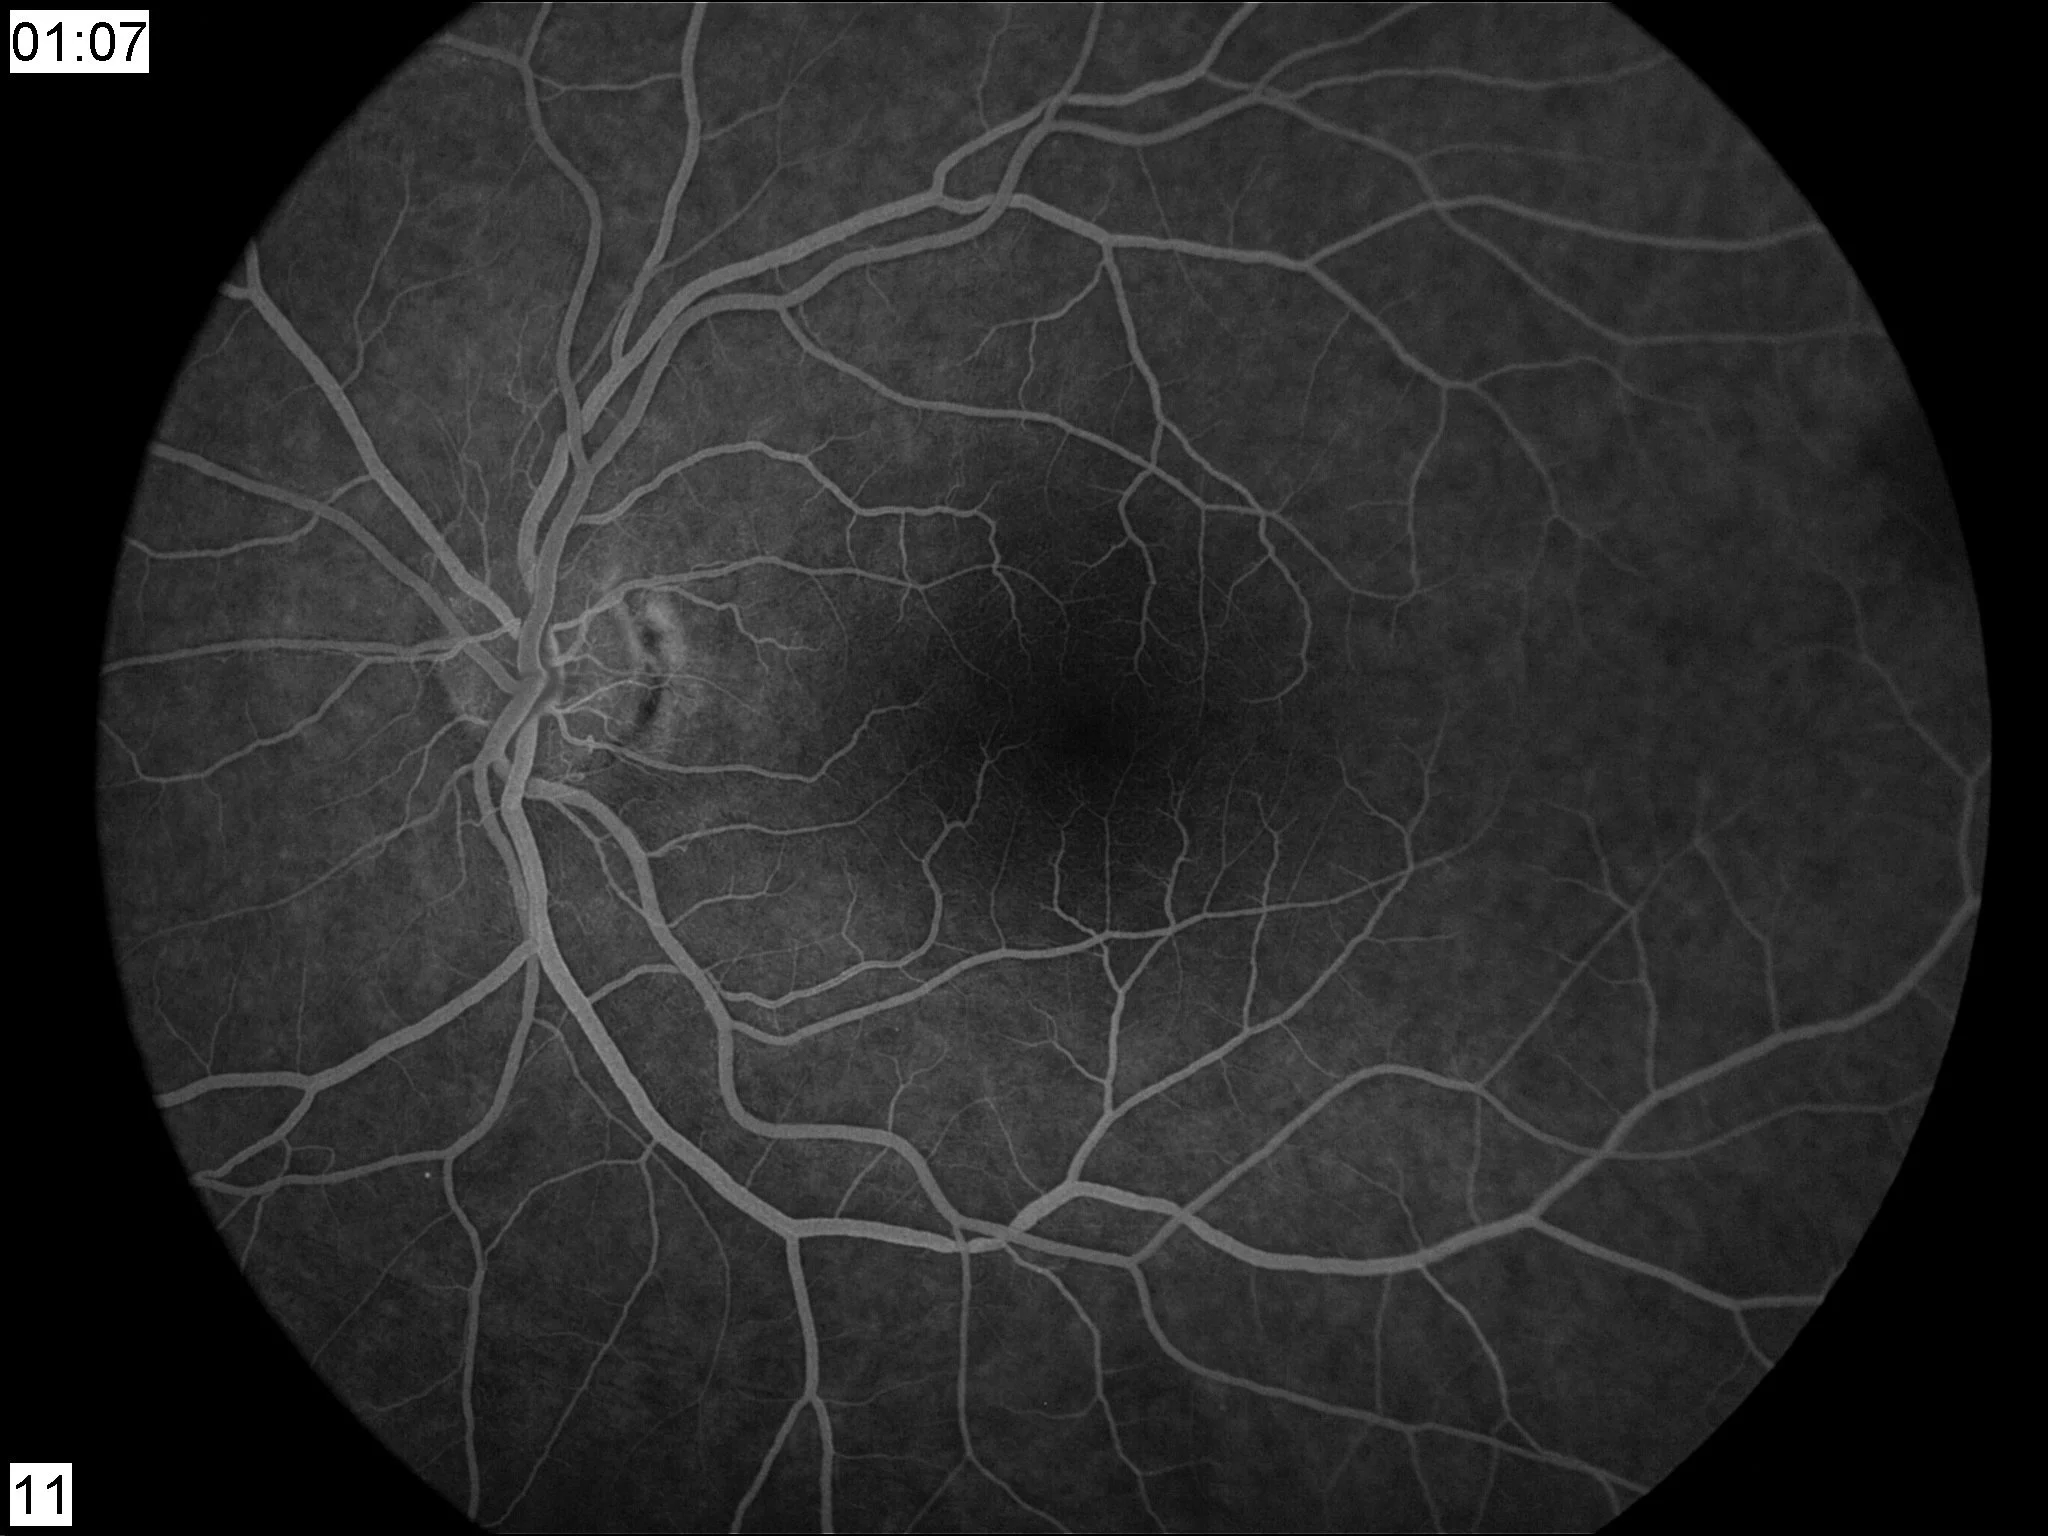

Φλουοροαγγειογραφία: επιβεβαιώνει ισχαιμία ή παθολογική διαρροή.